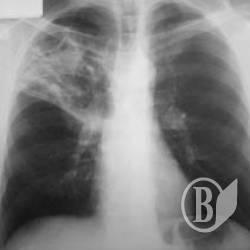

За 9 місяців поточного року медики зареєстрували в області 519 випадків захворювання на туберкульоз. 16 хворих – діти.

Майже 30% туберкульозу легень виявляється вже при розпаді легеневої тканини.

У 12-ти районах області відмічено зростання захворюваності, а у 5 з них ситуація критична. Це Куликівський, Варвинський, Козелецький, Борзнянський та Ічнянський райони.